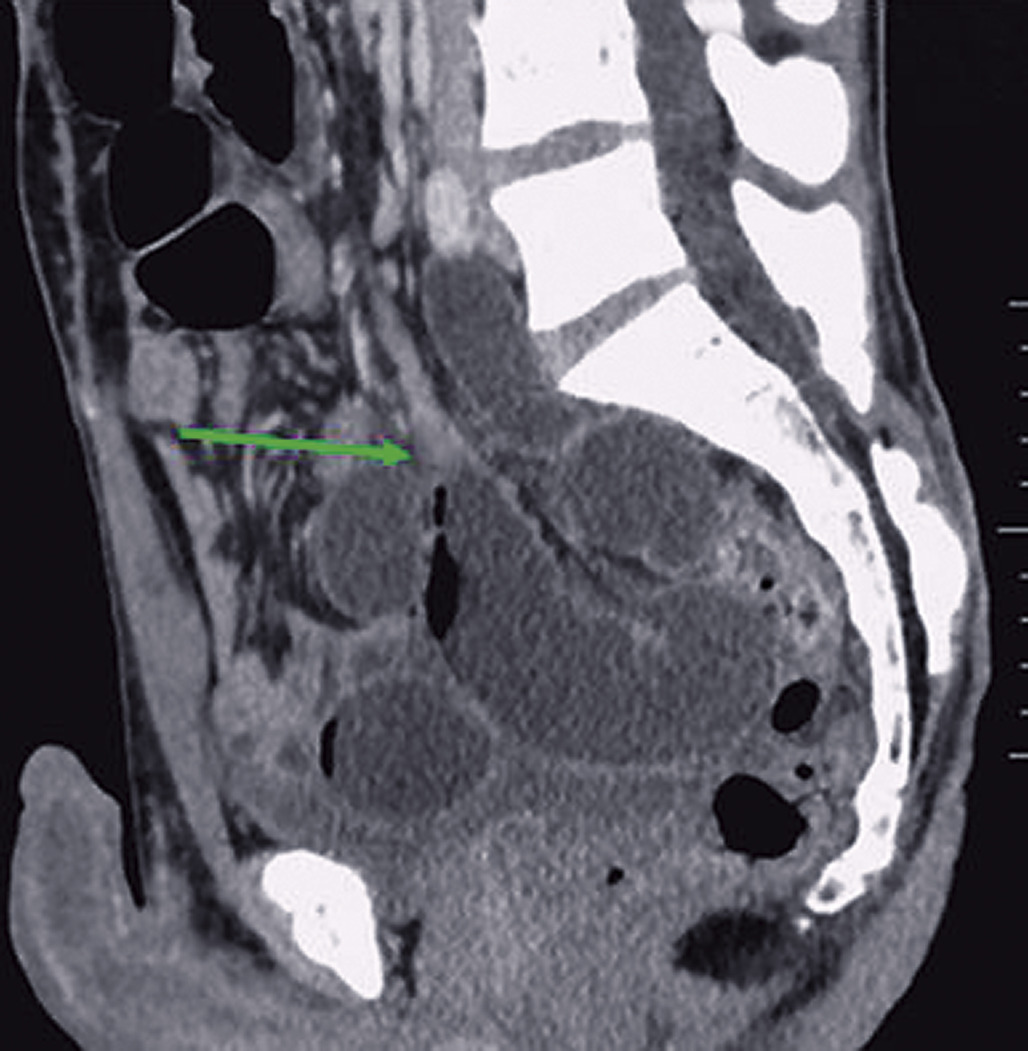

Tumeurs du grêle (fig. 3) : ces sont les tumeurs malignes primitives ou secondaires (15 % des occlusions du grêle).

Tomodensitométrie abdomino-pelvienne (fig. 4, 5) :

• 1) Elle fait le diagnostic positif de l’occlusion (présence d’anses grêles dilatées de diamètre supérieur ou égal à 25 mm si la valvule de Bauhin est incontinente et d’une partie du côlon de diamètre supérieur ou égal à 60 mm en amont de la tumeur).

• 2) Elle détermine la topographie (colique).

• 3) Elle détermine l’étiologie : l’adénocarcinome se traduit par un épaississement dédifférencié et sténosant de la paroi digestive en virole avec parfois infiltration de la graisse adjacente et adénomégalies péritumorales.

• 4) Elle identifie des signes de gravité (perforation, pneumatose pariétale, anomalies de rehaussement des anses spécialement sur le cæcum) (fig. 5).

• 5) Elle fait un bilan d’extension (fig. 5).